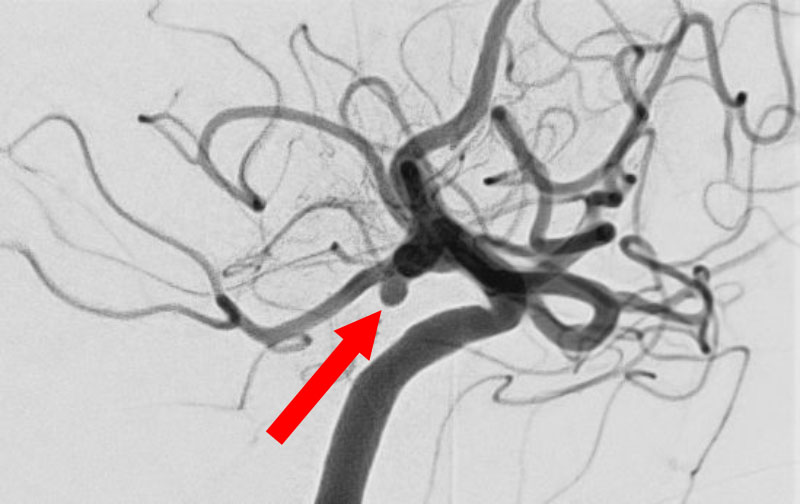

No.1600 手術前

No.1600 手術中

No.1600 手術後

'25年12月

くも膜下出血

脳底動脈瘤破裂

40代

救急外来